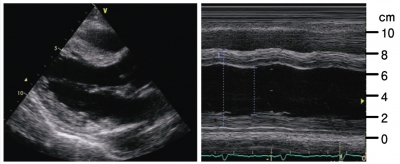

血液所見:赤血球 418 万、Hb 12.7 g/dL、白血球 11,300、血小板 20 万。血液生化学所見:AST 186 U/L、ALT 64 U/L、LD 995 U/L (基準 176〜353)、CK 352 U/L (基準 30〜140)、CK-MB 42 U/L(基準 20 以下)。CRP 11 mg/dL。心筋トロポニン T 迅速検査は陽性。胸部エックス線写真で心拡大と肺うっ血とを認める。来院時の心電図と心エコー図及び入院 14 日目の心エコー図を別に示す。